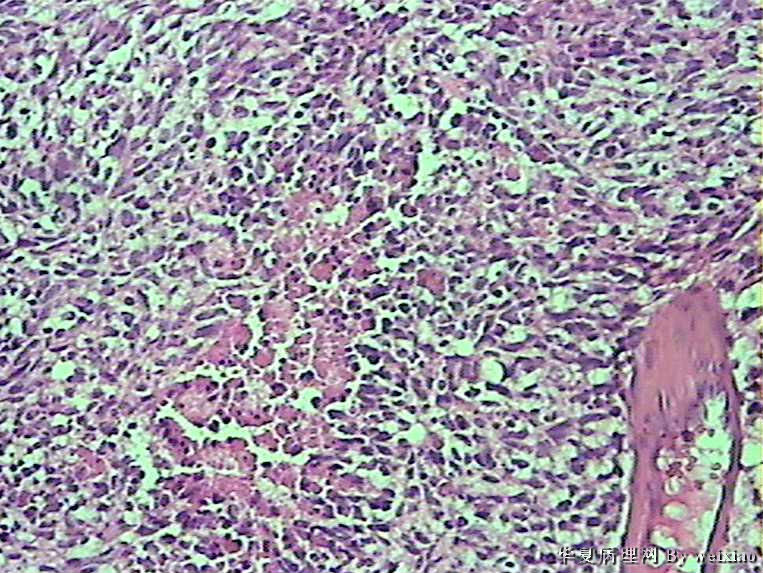

病史:男45岁,头痛2个月,手术所见:额叶占位性病变,与周围正常脑组  织的界限不清。

大体:灰白色碎组织一堆,质软,大小:2.5*1.8*1.3cm

• 额叶肿瘤图4

图4

×参考诊断

胶质母细胞瘤

坏死+细胞密度+异性+围绕血管现象。

The tumor cells are kind of spindle, need to rule out gliosarcoma, you need to check MRI films, do immunostain for GFAP, and vimentin. The vascular proliferation (VP) supports GBM.

肿瘤细胞呈梭形,血管增生明显,有坏死,符合胶质母。